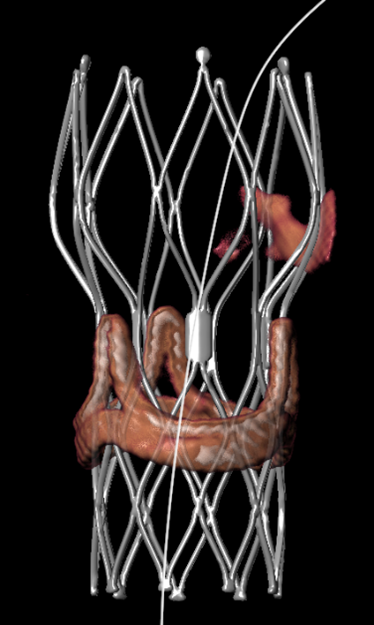

"With the rising rate of TAVI procedure being performed in South Asia, especially India, it becomes quite important to have an automated analysis workflow which is also accurate. With 3mensio Aortic Valve I can do this easily and with full control. What I like a lot is that 3mensio allows device visualization with the virtual valve functionality. The software enables me as an interventional cardiologist to compare and evaluate different sizes of various devices for the best fit.

Patients for TAVR in the subcontinent are younger, low risk and have often bicuspid aortic valves with small anatomy and bulky leaflets. This subgroup of patients are at higher chances of coronary obstruction during the index TAVR procedure. Also, they would require a repeat procedure (TAVR in TAVR) in future, when the THV degenerates. Assessing the risk of coronary occlusion is an important consideration in TAVR in TAVR procedures. The possibility for THV simulation helps answering above questions. It helps me in understanding the relationship of THV with coronaries in horizonal and vertical dimensions, thereby understanding the risk of coronary obstruction during the index TAVR procedure. It also upfront gives an insight about risk of coronary occlusion during TAVR in TAVR procedure, when the THV degenerates.

Another useful feature is the automatic annular plane segmentation with the cusp detection, which is a real time saver. This along with the simulated angio view and the automatic cusp overlap view gives optimal c-arm angulation which reduces procedure time and saves radiation.